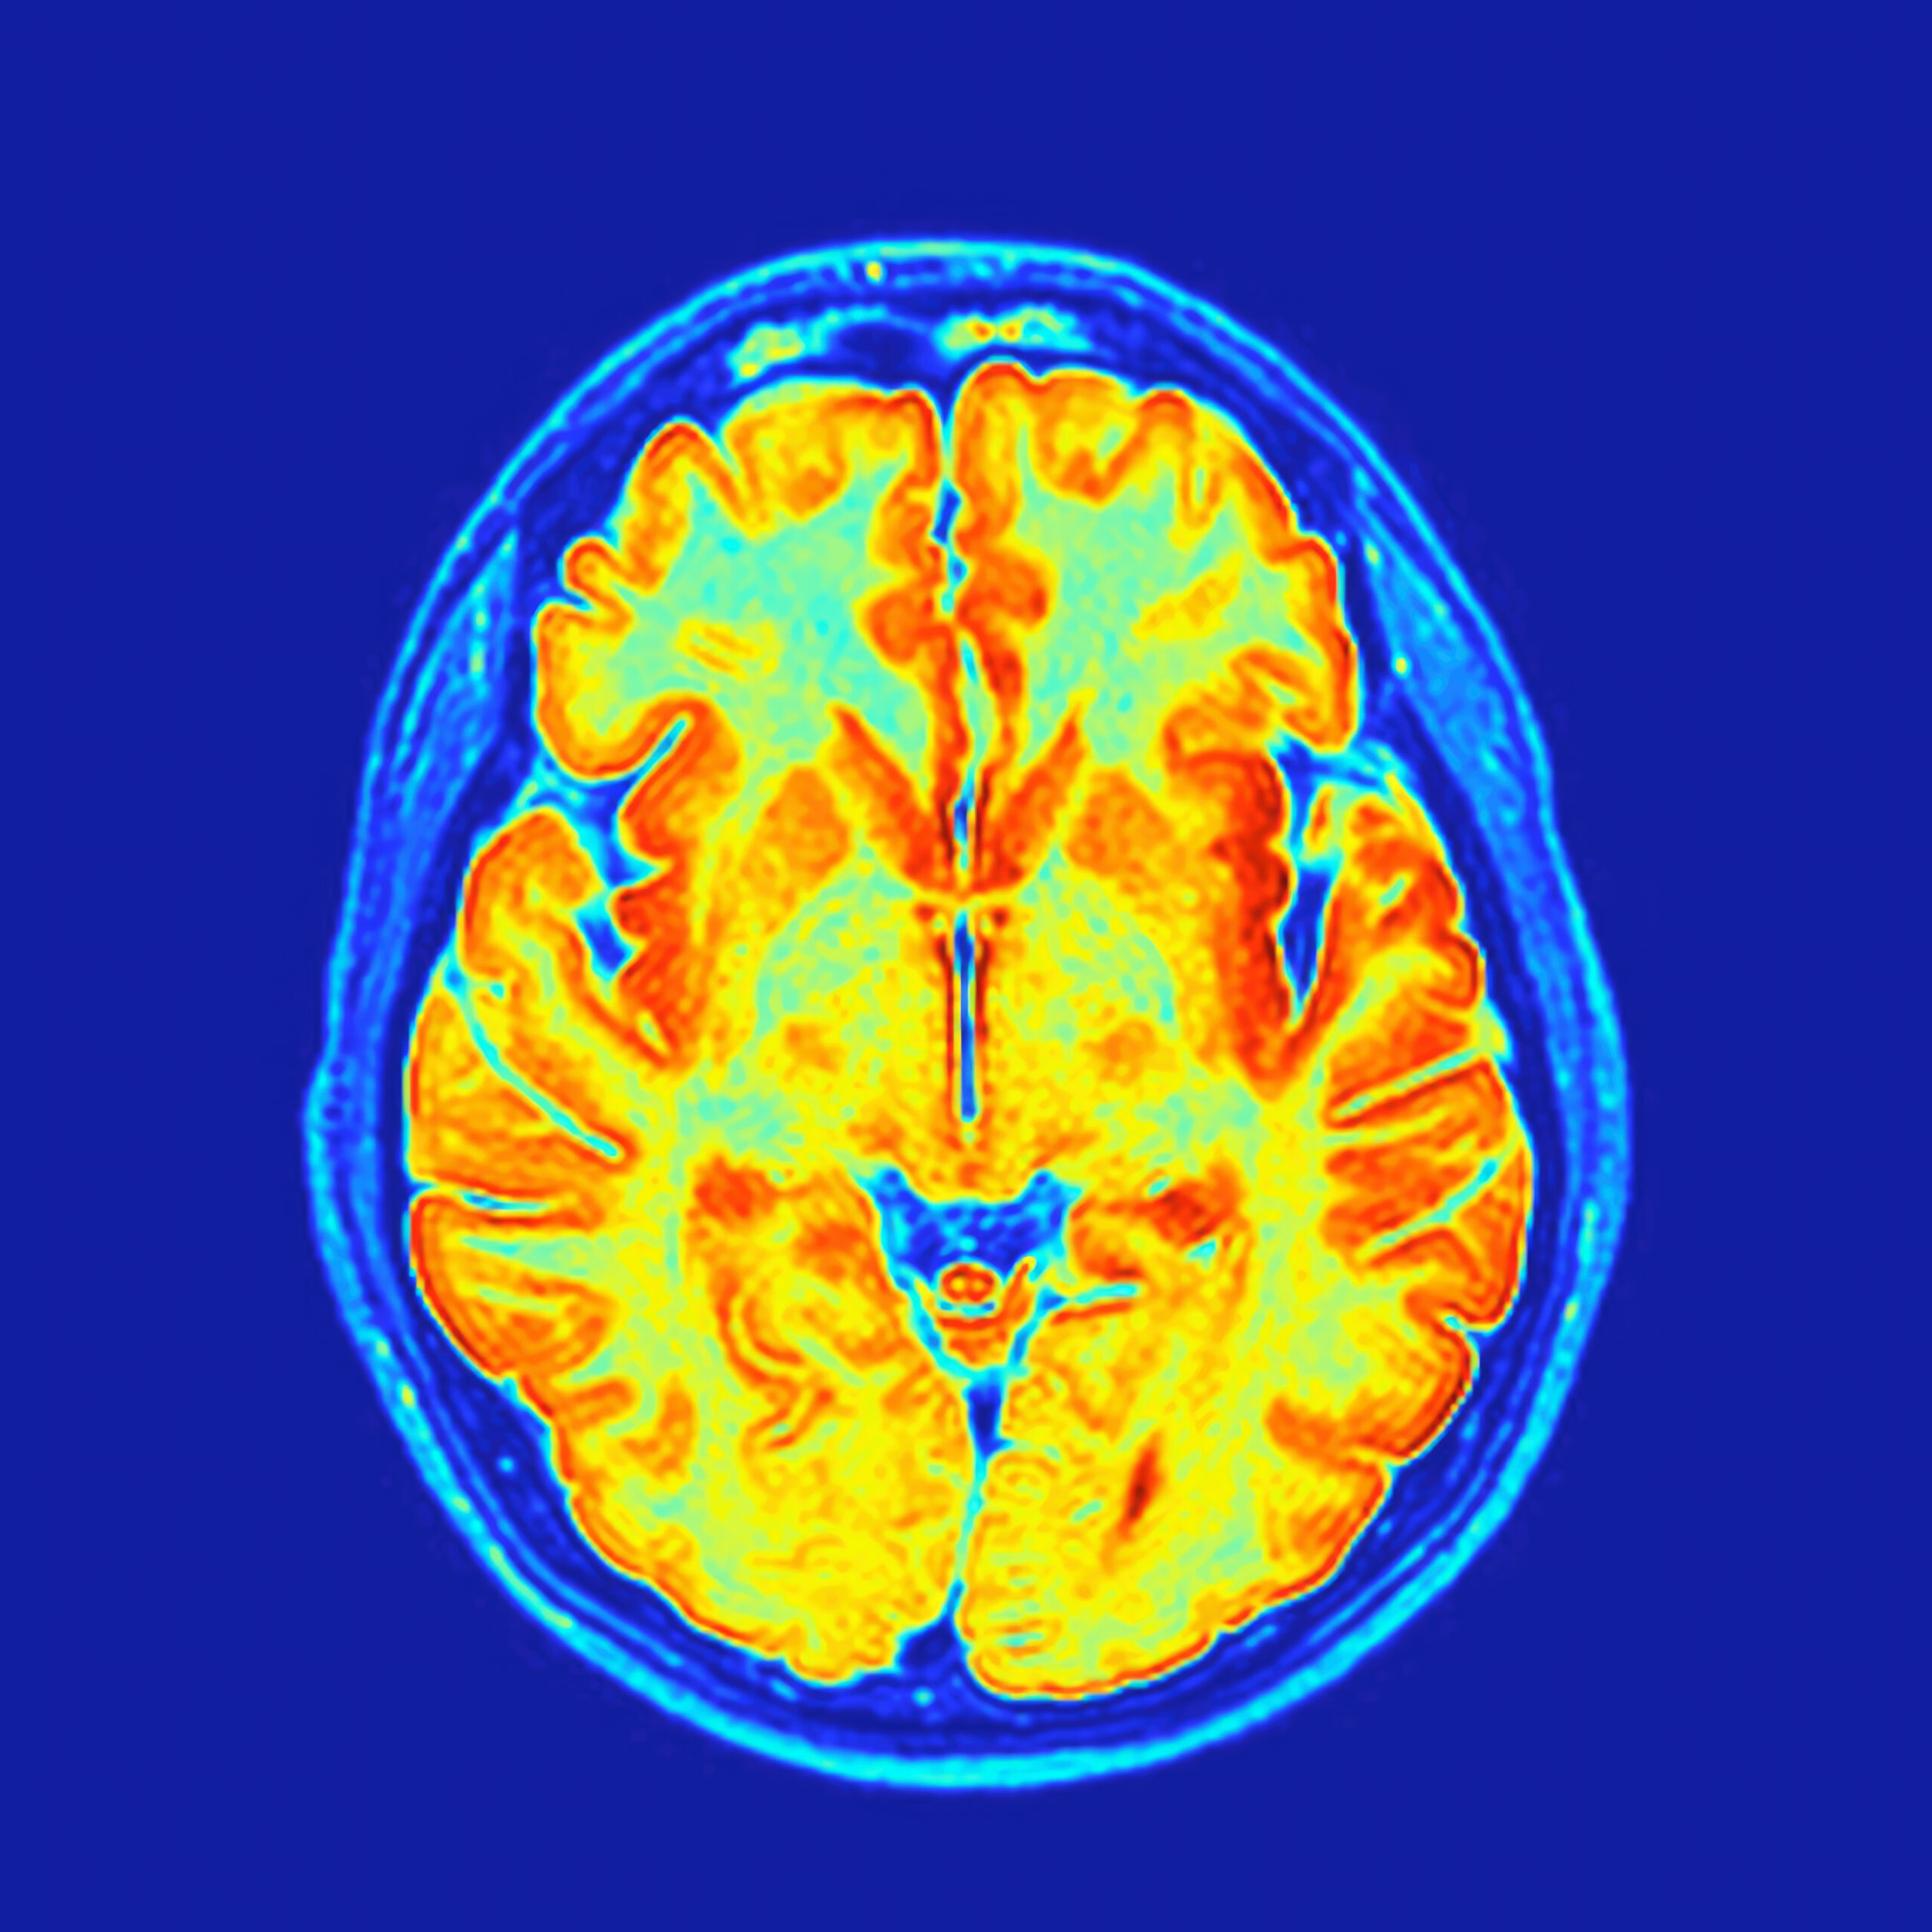

Bijoy Kundu, a UVA School of Medicine associate professor in the department of Radiology and Medical Imaging, presented ID-PET, a technology that combines brain imaging and AI, at the BioHub gathering.

Bijoy Kundu’s company, ID-PET, uses positron emission tomography—those familiar PET scan tubes that investigate how a body is functioning—and artificial intelligence to search for brain abnormalities. Based on small trials, Kundu reported two initial successes.

For patients whose blood pressure prevents them from taking epilepsy medications, surgery is the main option, he said, but fewer than half of patients want to risk brain surgery without convincing proof of future onset. However, “We are able to identify the seizure [zone] on sensor in patients who are drug-resistant,” Kundu said.

The technology can also predict glioma recurrence post-surgery more accurately than the clinical standard, he said.